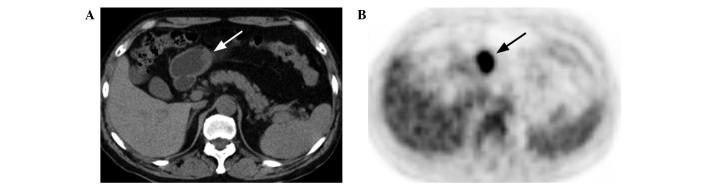

The role of F-fluorodeoxyglucose positron emission tomography/computed tomography (F-FDG PET/CT) in numerous malignant tumors, including gastric lymphoma, is well-established. However, there have been few studies with regard to the F-FDG PET/CT features of gastric lymphoma. The aim of the present study was to characterize the F-FDG PET/CT features of gastric lymphoma, which were compared with those of gastric cancer. Prior to treatment, F-FDG PET/CT was performed on 24 patients with gastric lymphoma and 43 patients with gastric cancer. The F-FDG PET/CT pattern of gastric wall lesions was classified as one of three types: Type I, diffuse thickening of the gastric wall with increased FDG uptake infiltrating more than one-third of the total stomach; type II, segmental thickening of the gastric wall with elevated FDG uptake involving less than one-third of the total stomach; and type III, local thickening of the gastric wall with focal FDG uptake. The incidence of the involvement of more than one region of the stomach was higher in the patients with gastric lymphoma than in those with gastric cancer. Gastric FDG uptake was demonstrated in 23 of the 24 patients (95.8%) with gastric lymphoma and in 40 of the 43 patients (93.0%) with gastric cancer. Gastric lymphoma predominantly presented with type I and II lesions, whereas gastric cancer mainly presented with type II and III lesions. The maximal thickness was larger and the maximal standard uptake value (SUV) was higher in the patients with gastric lymphoma compared with those with gastric cancer. A positive correlation between the maximal thickness and SUV was confirmed for the gastric cancer lesions, but not for the gastric lymphoma lesions. There was no difference in the maximal thickness and SUV of the gastric wall lesions between the patients without and with extragastric involvement, for gastric lymphoma and gastric cancer. Overall, certain differences exist in the findings between gastric lymphoma and gastric cancer patients on F-FDG PET/CT images, which may contribute to the identification of gastric lymphoma.

氟脱氧葡萄糖正电子发射断层扫描/计算机断层扫描(F-FDG PET/CT)在包括胃淋巴瘤在内的众多恶性肿瘤中的作用已得到充分证实。然而,关于胃淋巴瘤的F-FDG PET/CT特征的研究却很少。本研究的目的是描述胃淋巴瘤的F-FDG PET/CT特征,并与胃癌的特征进行比较。治疗前,对24例胃淋巴瘤患者和43例胃癌患者进行了F-FDG PET/CT检查。胃壁病变的F-FDG PET/CT模式分为三种类型之一:I型,胃壁弥漫性增厚,FDG摄取增加,浸润超过全胃的三分之一;II型,胃壁节段性增厚,FDG摄取增加,累及全胃不到三分之一;III型,胃壁局部增厚,有局灶性FDG摄取。胃淋巴瘤患者胃多区域受累的发生率高于胃癌患者。24例胃淋巴瘤患者中有23例(95.8%)出现胃FDG摄取,43例胃癌患者中有40例(93.0%)出现胃FDG摄取。胃淋巴瘤主要表现为I型和II型病变,而胃癌主要表现为II型和III型病变。与胃癌患者相比,胃淋巴瘤患者的最大厚度更大,最大标准摄取值(SUV)更高。在胃癌病变中证实最大厚度与SUV之间存在正相关,但在胃淋巴瘤病变中未证实。对于胃淋巴瘤和胃癌,有无胃外受累患者的胃壁病变最大厚度和SUV无差异。总体而言,胃淋巴瘤和胃癌患者在F-FDG PET/CT图像上的表现存在一定差异,这可能有助于胃淋巴瘤的识别。